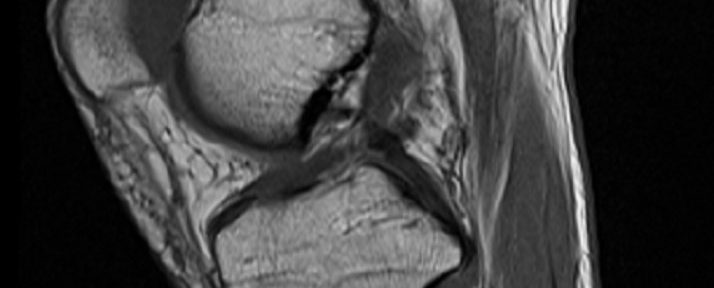

MRI evaluation

Both the tibial and femoral stumps of the torn anterior cruciate ligament appear to be fused with the posterior cruciate ligament. In this case, the anterior cruciate ligament stumps did not fuse together, but the knee regained stability through the fusion with the posterior cruciate ligament. In the medial meniscus, damage to the inner edge only spread to the outer edge and reached the red zone with high blood flow, so natural healing can be expected in the future.